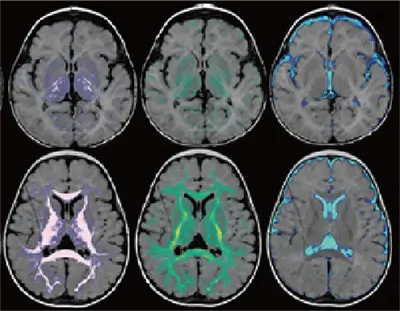

負担の少ない脳イメージングSyMRI

検査時間が数分と短く、また、従来のCTやMRIでは見えなかった脳の発達の様子(ミエリンの成熟など)を鮮明なカラー画像で見ることもできます。